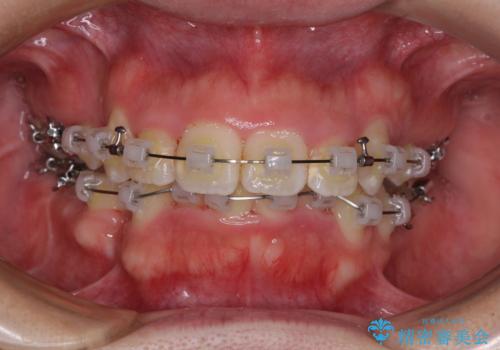

- 矯正装置

- クリアブラケット

気になっていた八重歯は装置装着から3か月ほどで解消されました。